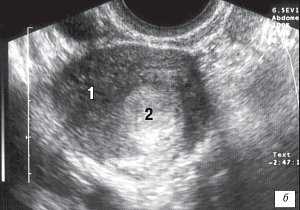

Другой важный признак рассматриваемой патологии - это асимметрия толщины боковых стенок матки (рис. 2 а, б). Она варьировалась от 0,4 до 1,1 см. Причем более толстой была та стенка матки, где отсутствовал ее "нормальный полурог".

а) Толщина боковых стенок 0,5 см.

б) Толщина боковых стенок 1,1 см.